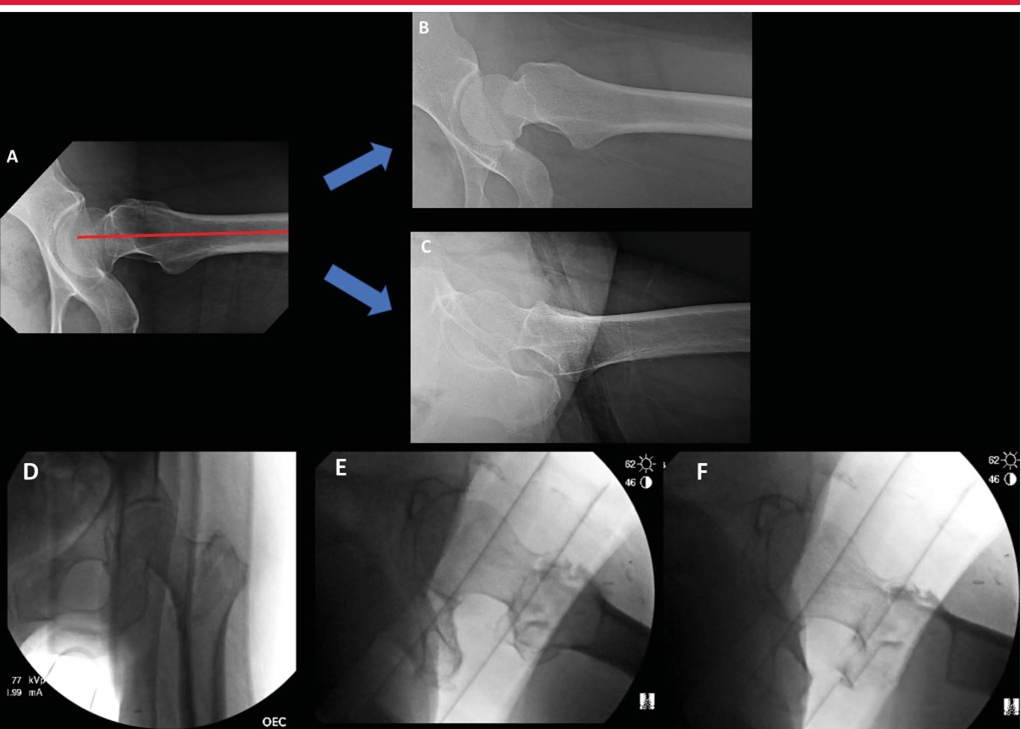

Для оценки морфологии перелома необходима специализированная рентгенография бедра. Хотя взаимосвязь между кончиком большого вертела и центром головки бедренной кости обычно копланарная, переднезадняя рентгенограмма таза или контралатеральная рентгенограмма бедра может помочь оценить нативную анатомию и потенциальный вальга-тазик или варум тазика (coxa vara) (нормальная диафиз шейного отдела). угол на картинке ниже, B coxa valgus, C coxa varus)

Тракционные рентгенограммы внутренней ротации особенно полезны при предоперационном планировании. Khurana и соавт. продемонстрировали, что тракционные рентгенограммы с внутренней ротацией значительно улучшают диагностическую точность, надежность и согласованность между наблюдателями при классификации переломов проксимального отдела бедренной кости. Кроме того, предоперационные тракционные рентгенограммы могут помочь хирургу определить, когда маневры закрытой репозиции будут успешными (рис. 2).

Интраоперационная боковая рентгеноскопия бедра для оценки репозиции и имплантата. А. Боковое изображение, наиболее подходящее для имплантата, демонстрирующее коллинеарность головки, шейки бедренной кости и оси бедренной кости. Б. Боковая рентгенограмма того же тазобедренного сустава во внутренней ротации. C: Повернутое наружу боковое изображение того же бедра, оптимальное для оценки переднемедиальной кортикальной поддержки и репозиции вертельных переломов. D–F: интраоперационные рентгеноскопические изображения, полученные в положении лежа на столе для переломов, показывающие вид в прямой проекции (D), боковой вид имплантата (E) и боковой репозиции (F).